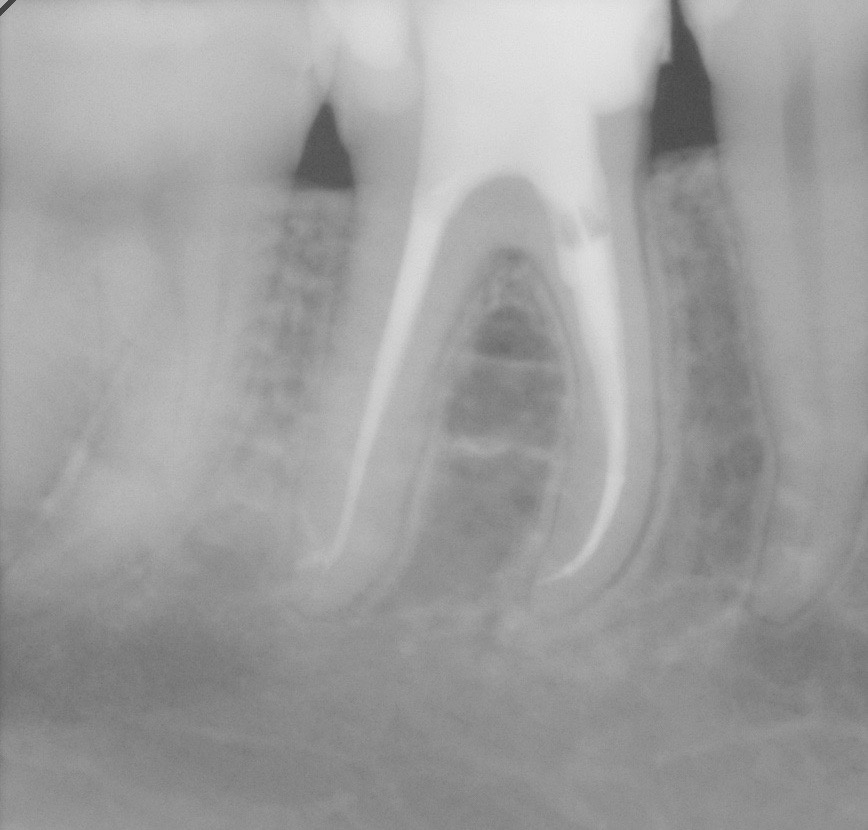

Eine absolute Extraktionsindikation stellt die Wurzellängsfraktur bei einwurzeligen Zähnen dar. Differenzierter zu betrachten ist die Wurzellängsfraktur eines mehrwurzeligen Zahnes. Bei entsprechend günstigen Voraussetzungen kann mitunter auch die Option einer Hemisektion in Betracht gezogen werden. In die Entscheidungsfindung sollten auch immer Überlegungen zur langfristigen Planung einfließen. Die prothetische Wertigkeit eines Molaren ist beispielsweise durch die Entfernung einer Wurzel deutlich herabgesetzt. Klinisch imponiert bei Längsfrakturen der sogenannte „Kamineffekt“. Bei zirkulär sonst unauffälligen Sondierungstiefen fällt man entlang des Frakturverlaufs mit der Messsonde in den osteolytisch entstandenen „Kamin“ (Abb. 13). Auch im hier dargestellten Fall (Abb. 16) war nach Auswertung aller relevanten Aspekte (Ursache, Prognose, langfristige prothetische Planung) die frühzeitige Extraktion Mittel der Wahl um die Voraussetzungen für eine anschließende Implantation nicht negativ zu beeinflussen.